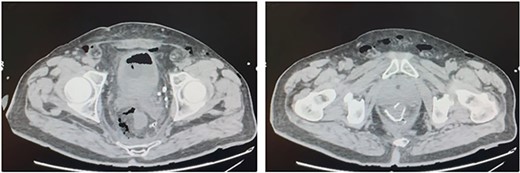

A 75-year-old Caucasian man was referred to our department on May 2022 because of a positive fecal occult blood test; subsequent colonoscopy showed an endoluminal substenosing lesion, located at sigmoid-rectal junction and extended distally for 5 cm. The tumoral bulk appeared centrally ulcerated and occupied more than three-fourth of the rectal circumference. The panel of biopsies resulted positive for well-differentiated adenocarcinoma. An angio-CT scan confirmed the presence of a sigmoid-rectal wall thickening, extended distally for about 6 cm, with significative narrowing of colonic lumen. Lateral spread appeared limited to the muscolaris propria, whereas the mesorectal component was unaffected; the presence of T2 lesion at preoperative diagnostic work-up was confirmed by MRI while neither hepatic nor pulmonary metastasis were detected. Tumor markers were within normal range. At physical examination, the patient appeared overweight (BMI 30.5), with no other significative comorbidity. Pre-operative staging led the Multidisciplinary Tumor Board to authorise a surgical approach. The patient underwent laparoscopic low anterior rectal resection with total mesorectal excision, with transanal end-to-end stapled colorectal anastomosis (7 cm from the anal verge) and ileostomy. Histological report of resected specimen confirmed the diagnosis of a G2 rectal adenocarcinoma, staged as pT3 pN1a R0, whereas the quality of mesorectal excision was graded as 3 (complete mesorectal fascia) according to Quirke classification. On the fifth post-operative day, the patient developed an increase in body temperature (37.8°C), in WBC count (10 × 103/uL) and in CRP plasmatic levels (6.63 mg/dL), as well as a corpuscular discharge from perianastomotic drainage; at physical examination, the patient showed a moderate tenderness on lower left abdomen with no clear signs of peritonitis. Early abdominal angio-CT scan showed a 15-mm discontinuity on the posterior wall of colorectal anastomosis, with perirectal fluid and extraluminal gas collection (Fig. 1). Low-flow endoscopic exploration confirmed the anastomotic wall defect in the right postero-lateral side, connected to a cavity filled with necrotic tissue (Fig. 2). Given the presence of ileostomy and perianastomotic surgical drainage and the absence of peritonitis signs with proper control of patient’s hemodinamics, we opted for a non-surgical treatment. On the sixth post-operative day, the patient underwent an Endo-SPONGE® device placement into the AL cavity, performed with TAMIS approach [7]. With the patient in lithotomy position, a GelPOINT® path transanal access platform was positioned; laparoscopic insufflation pressure was set at 10 mmHg. The right posterolateral anastomotic wall defect was visualised (Fig. 3), then the AL cavity was carefully measured (3 cm × 4 cm), washed with saline solution and explored up to the tip of surgical drainage. The polyurethane sponge was positioned under laparoscopic vision and then connected to the vacuum suction system, set at −40 mmHg. The Endo-SPONGE® device was replaced every 72 h for 2 weeks, then every 96 h for another 10 days; size and shape of the device were modified and gradually reduced according to the decreasing size of the cavity. Control CT scan and rectosigmoidoscopy confirmed the almost complete obliteration of the AL cavity. The Endo-SPONGE® device and the abdominal drainage were removed on the 25th post-operative day and the patient was then discharged without further complications. The patient has been addressed to adjuvant treatment protocol; a 3-month control CT scan showed neither distant metastases nor residual perirectal cavity. Once adjuvant treatment is completed, patient will be enrolled for colorectal anastomotic check and closure of ileostomy.

Contrast CT scan: ‘Abundant fluid-air presence in the presacral space and in the mesorectum at the level of the colo-rectal anastomosis, and a discontinuity on the posterior side of the colonic wall’.